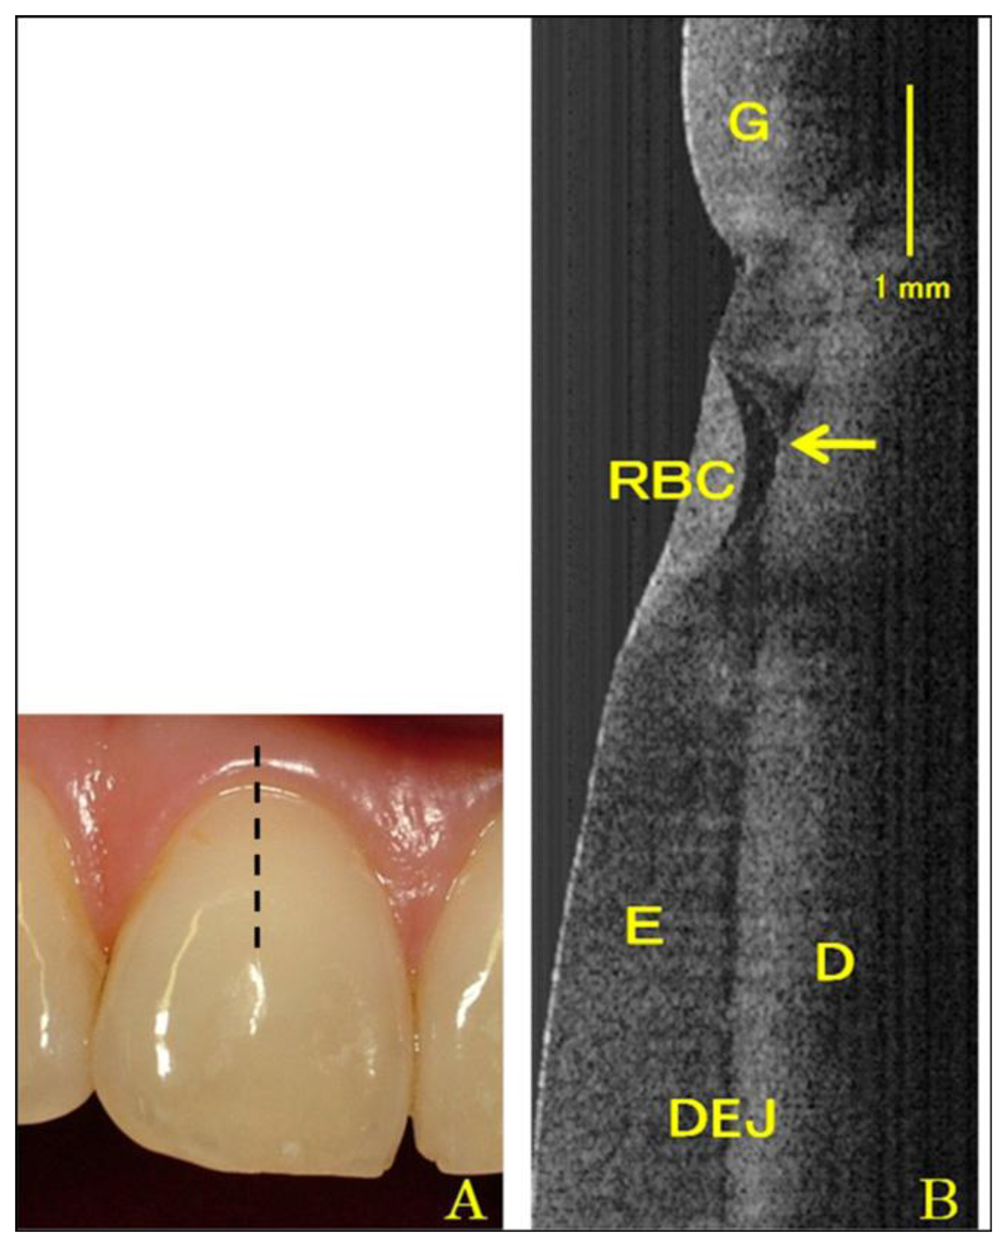

Figure 3 illustrates a tooth structure. Colson et al. first reported the 1,310 nm TD-OCT image of teeth and compared them with a photomicrograph under 17 μm resolution [26]. They only examined the characteristics of the oral structure surface because of the insufficient penetrating depth. The in vitro images of enamel-cementum and gingiva-tooth interfaces in a porcine model were shown. Otis et al. presented the first in vivo OCT images of human dental tissues [47]. The axial resolution was 12 μm with 1,310 nm center wavelength. They obtained a smaller but deeper (3 mm) tooth image. Their OCT images provided visual recording of the dentin-enamel junction (DEJ) and periodontal structures. Feldchteine et al. demonstrated that hard palate mucosa and gingiva mucosa could be visualized [45]. The OCT images showed the hard palate mucosa. The squamous epithelium appears as the 170 mm top layer above the 200 mm thick lamina propria. OCT images also displayed gingiva mucosa to a depth of 500 μm, although the epithelium and lamina propria were not well differentiated in their scans. Moreover, they also presented the polarization imaging of normal dental hard tissue. OCT images in normal polarization scan mode showed that enamel, dentin, and DEJ were clearly visible. Warren et al. provided more detail tooth structure along the vertical axis [48]. The axial structure from enamel to dentin and cementum to dentin was revealed.